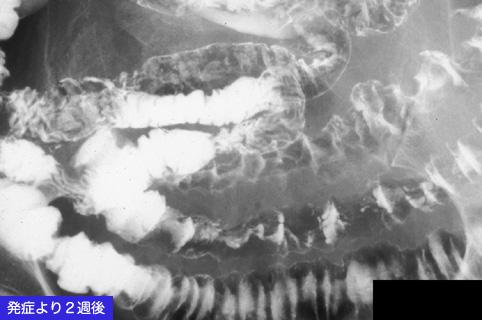

疾病(病理主体)的分类炎症性・溃疡性疾患/缺血性大肠炎

部位(按器官分)小肠/回肠

检查方法X线